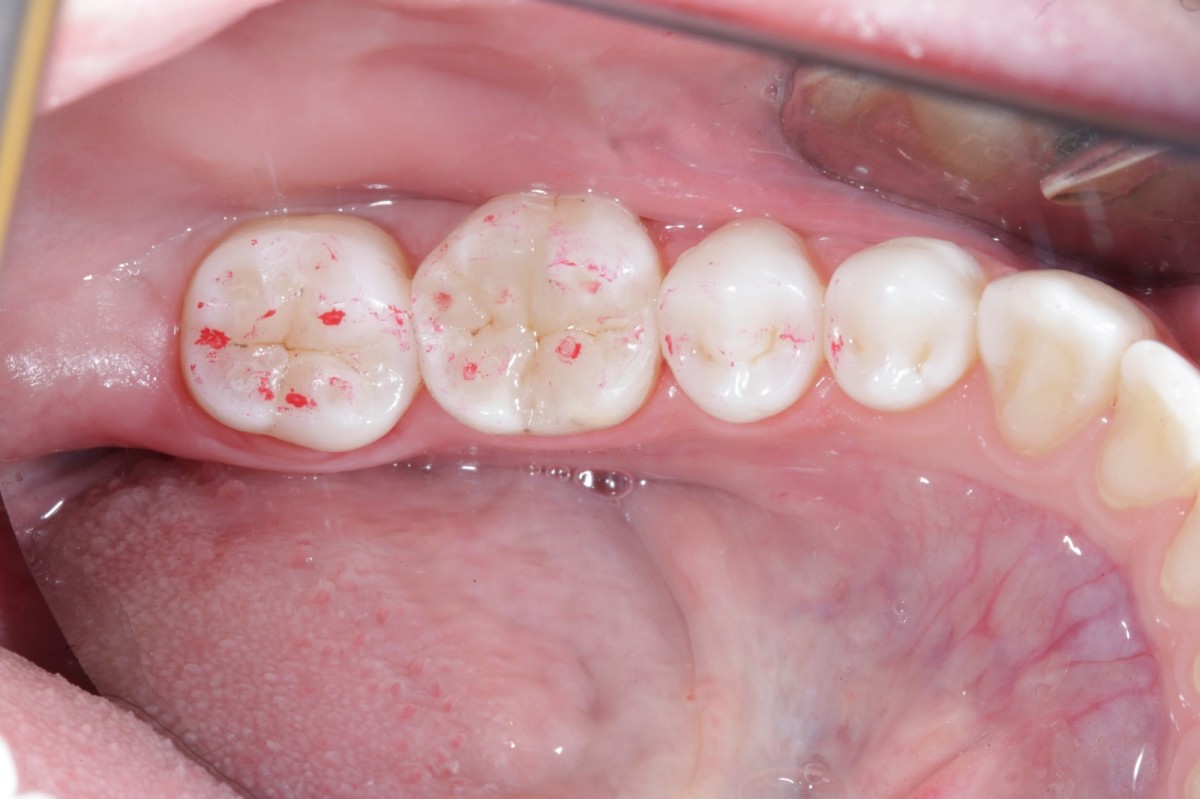

During the visit, consisting of the physical examination and instrumental examinations such as radiographs bitewings, thermal tests and compression tests (to exclude the presence of typical symptoms of a crack) at the level of the fourth quadrant, she has: amalgam restoration on dental element 4.6 associated with primary mesial caries and primary occlusal caries on 4.7.

The symptoms are not clearly identifiable by the patient but they can be traced back to dental elements 4.6 through diagnostic tests.